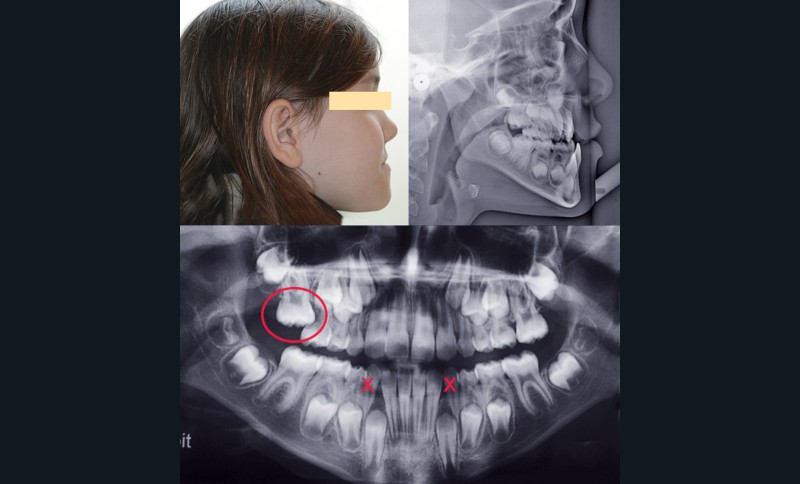

Cependant, la pose des plaques a été difficile du fait de la finesse du contrefort zygomatique et du peu de hauteur alvéolaire, en particulier au niveau du secteur I du fait de la rétention de la 16 (fig. 1).

Dès l’évolution des canines mandibulaires, les plaques ont été fixées, et 3 semaines après, malgré une grande sensibilité au niveau du secteur I, la mécanique élastique de classe III a été commencée (fig. 2).

Après 6 mois d’orthopédie, la plaque au niveau du secteur I, qui a toujours été défaillante, devient mobile et finit par se débricoler. De ce fait, les élastiques du côté gauche ont davantage fonctionné ; il en résulte une déviation du milieu incisif mandibulaire à gauche (fig. 3).

Une nouvelle plaque a été fixée mais aussitôt reperdue. De ce fait, nous avons décidé de continuer avec une phase de finition multibague (fig. 4).